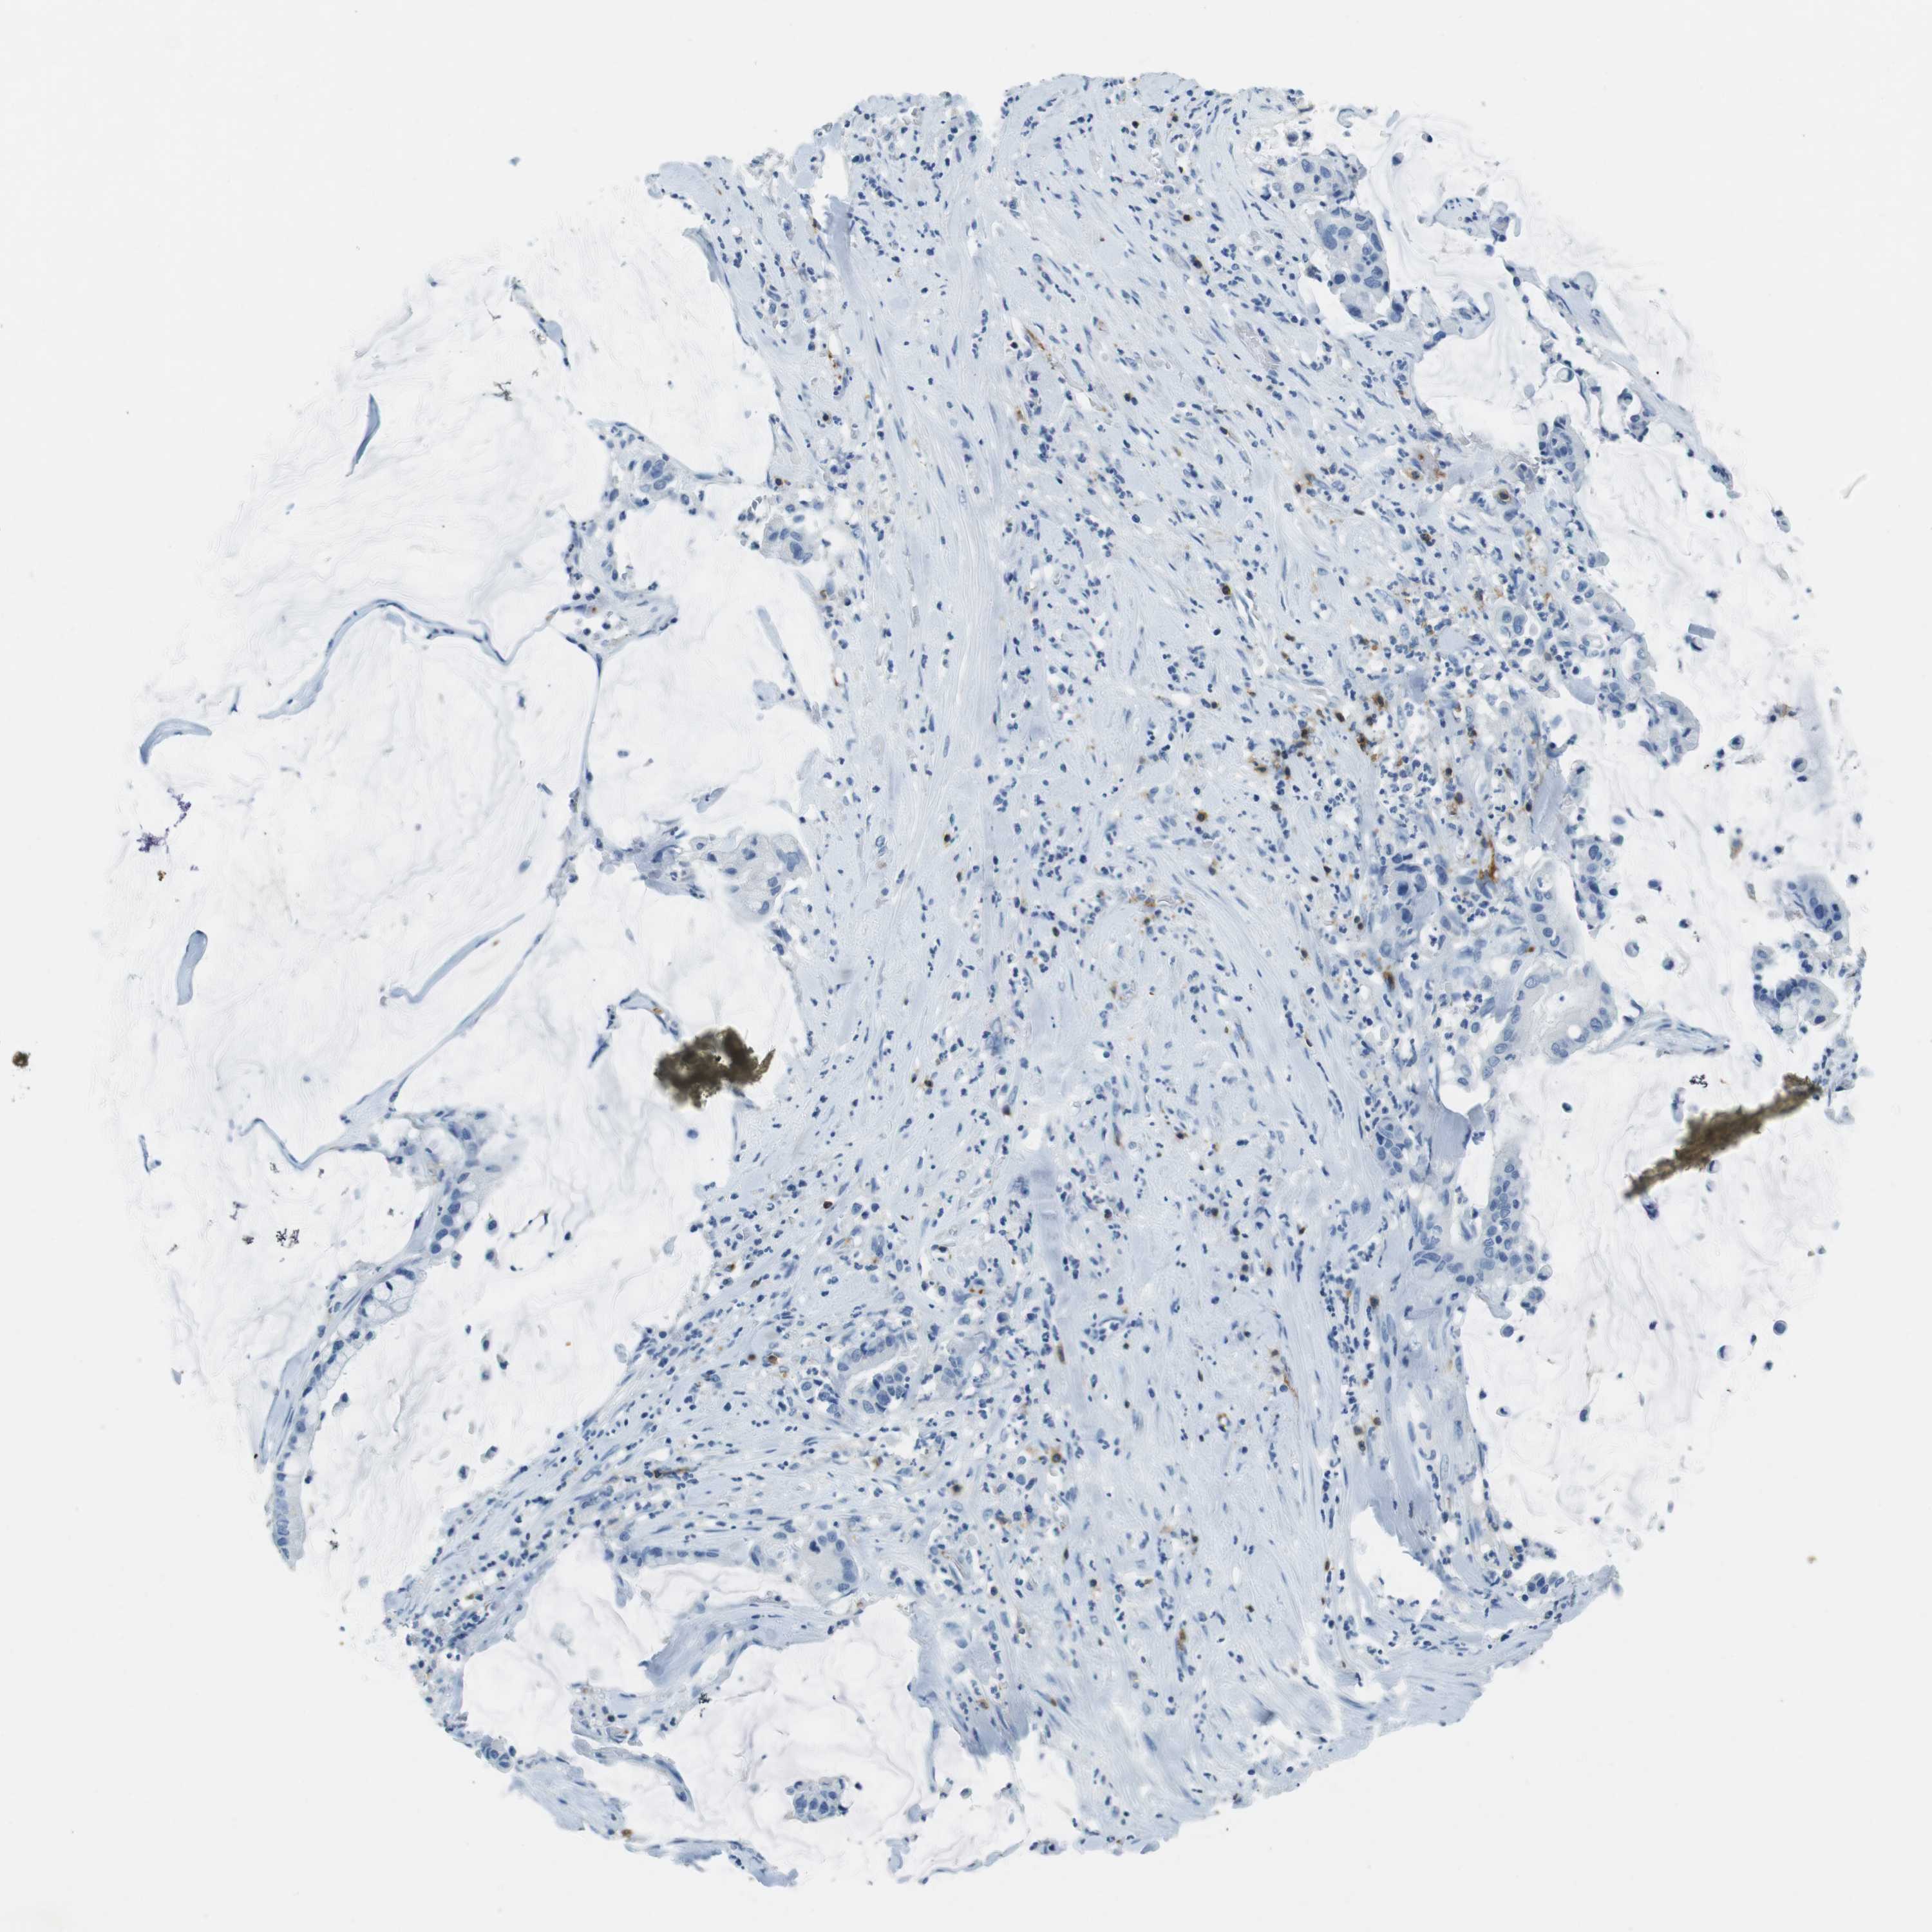

PANCREATIC CANCER - Protein expressioni

A mouse-over function shows sample information and annotation data. Click on an image to view it in a full screen mode. Samples can be filtered based on level of antibody staining by selecting one or several of the following categories: high, medium, low and not detected. The assay and annotation is described here.

Note that samples used for immunohistochemistry by the Human Protein Atlas do not correspond to samples in the TCGA dataset.

Antibody stainingi

Antibody staining in the annotated cell types in the current human tissue is reported as not detected, low, medium, or high, based on conventional immunohistochemistry profiling in selected tissues. This score is based on the combination of the staining intensity and fraction of stained cells.

Each image is clickable and will lead to virtual microscopy that enables deeper exploration of all samples and also displays staining intensity scores, fraction scores and subcellular localization as well as patient and tissue information for each sample.

Antibody HPA011157

Antibody CAB002223

Antibody CAB012978

Antibody CAB079960

Adenocarcinoma, NOS

Adenocarcinoma, metastatic, NOS